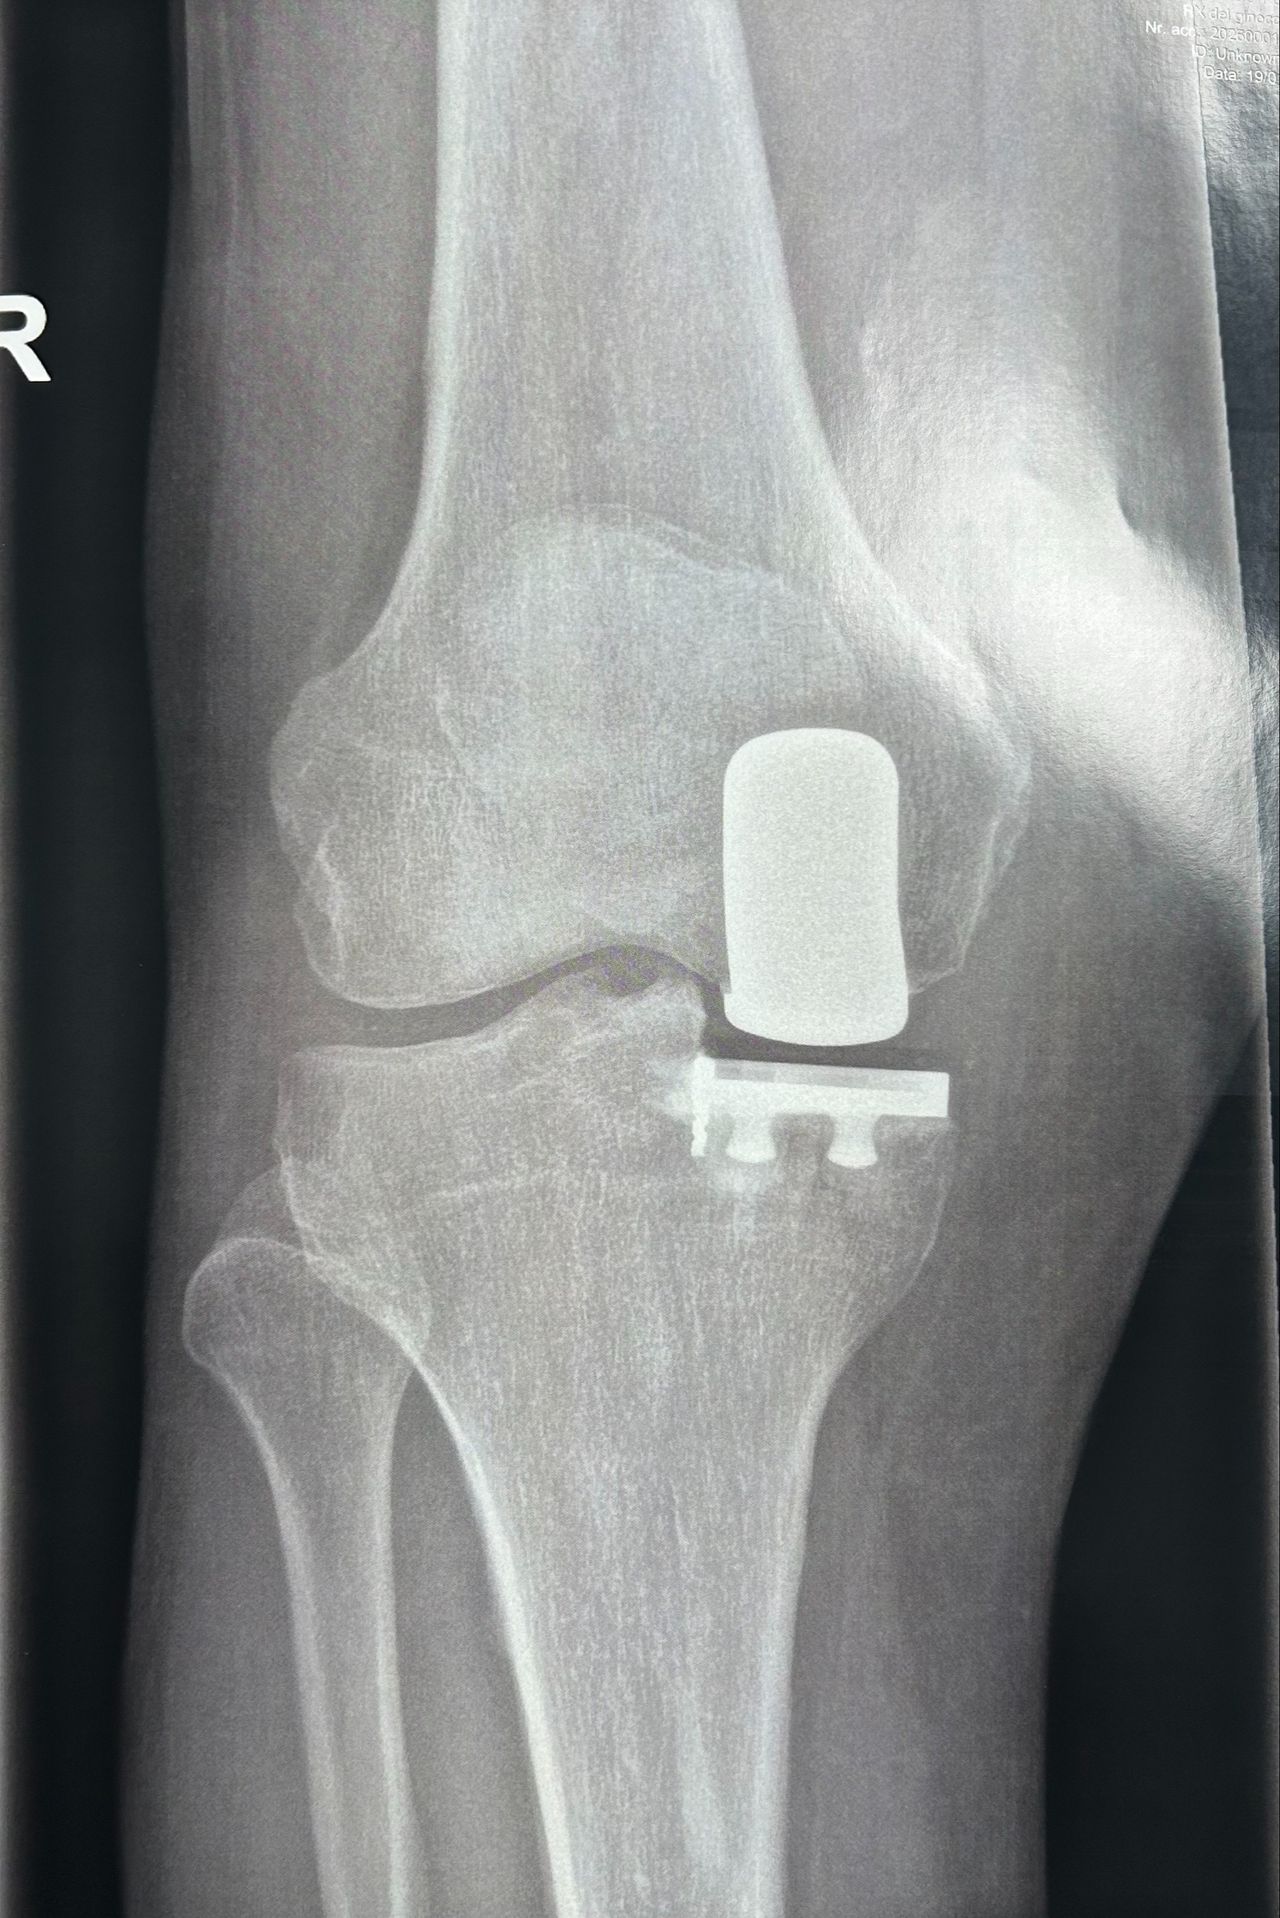

Foto e video

Per una maggiore completezza della visita è utile avere a dispozione almeno una Radiografia standard o Risonanza Magnetica recenti.